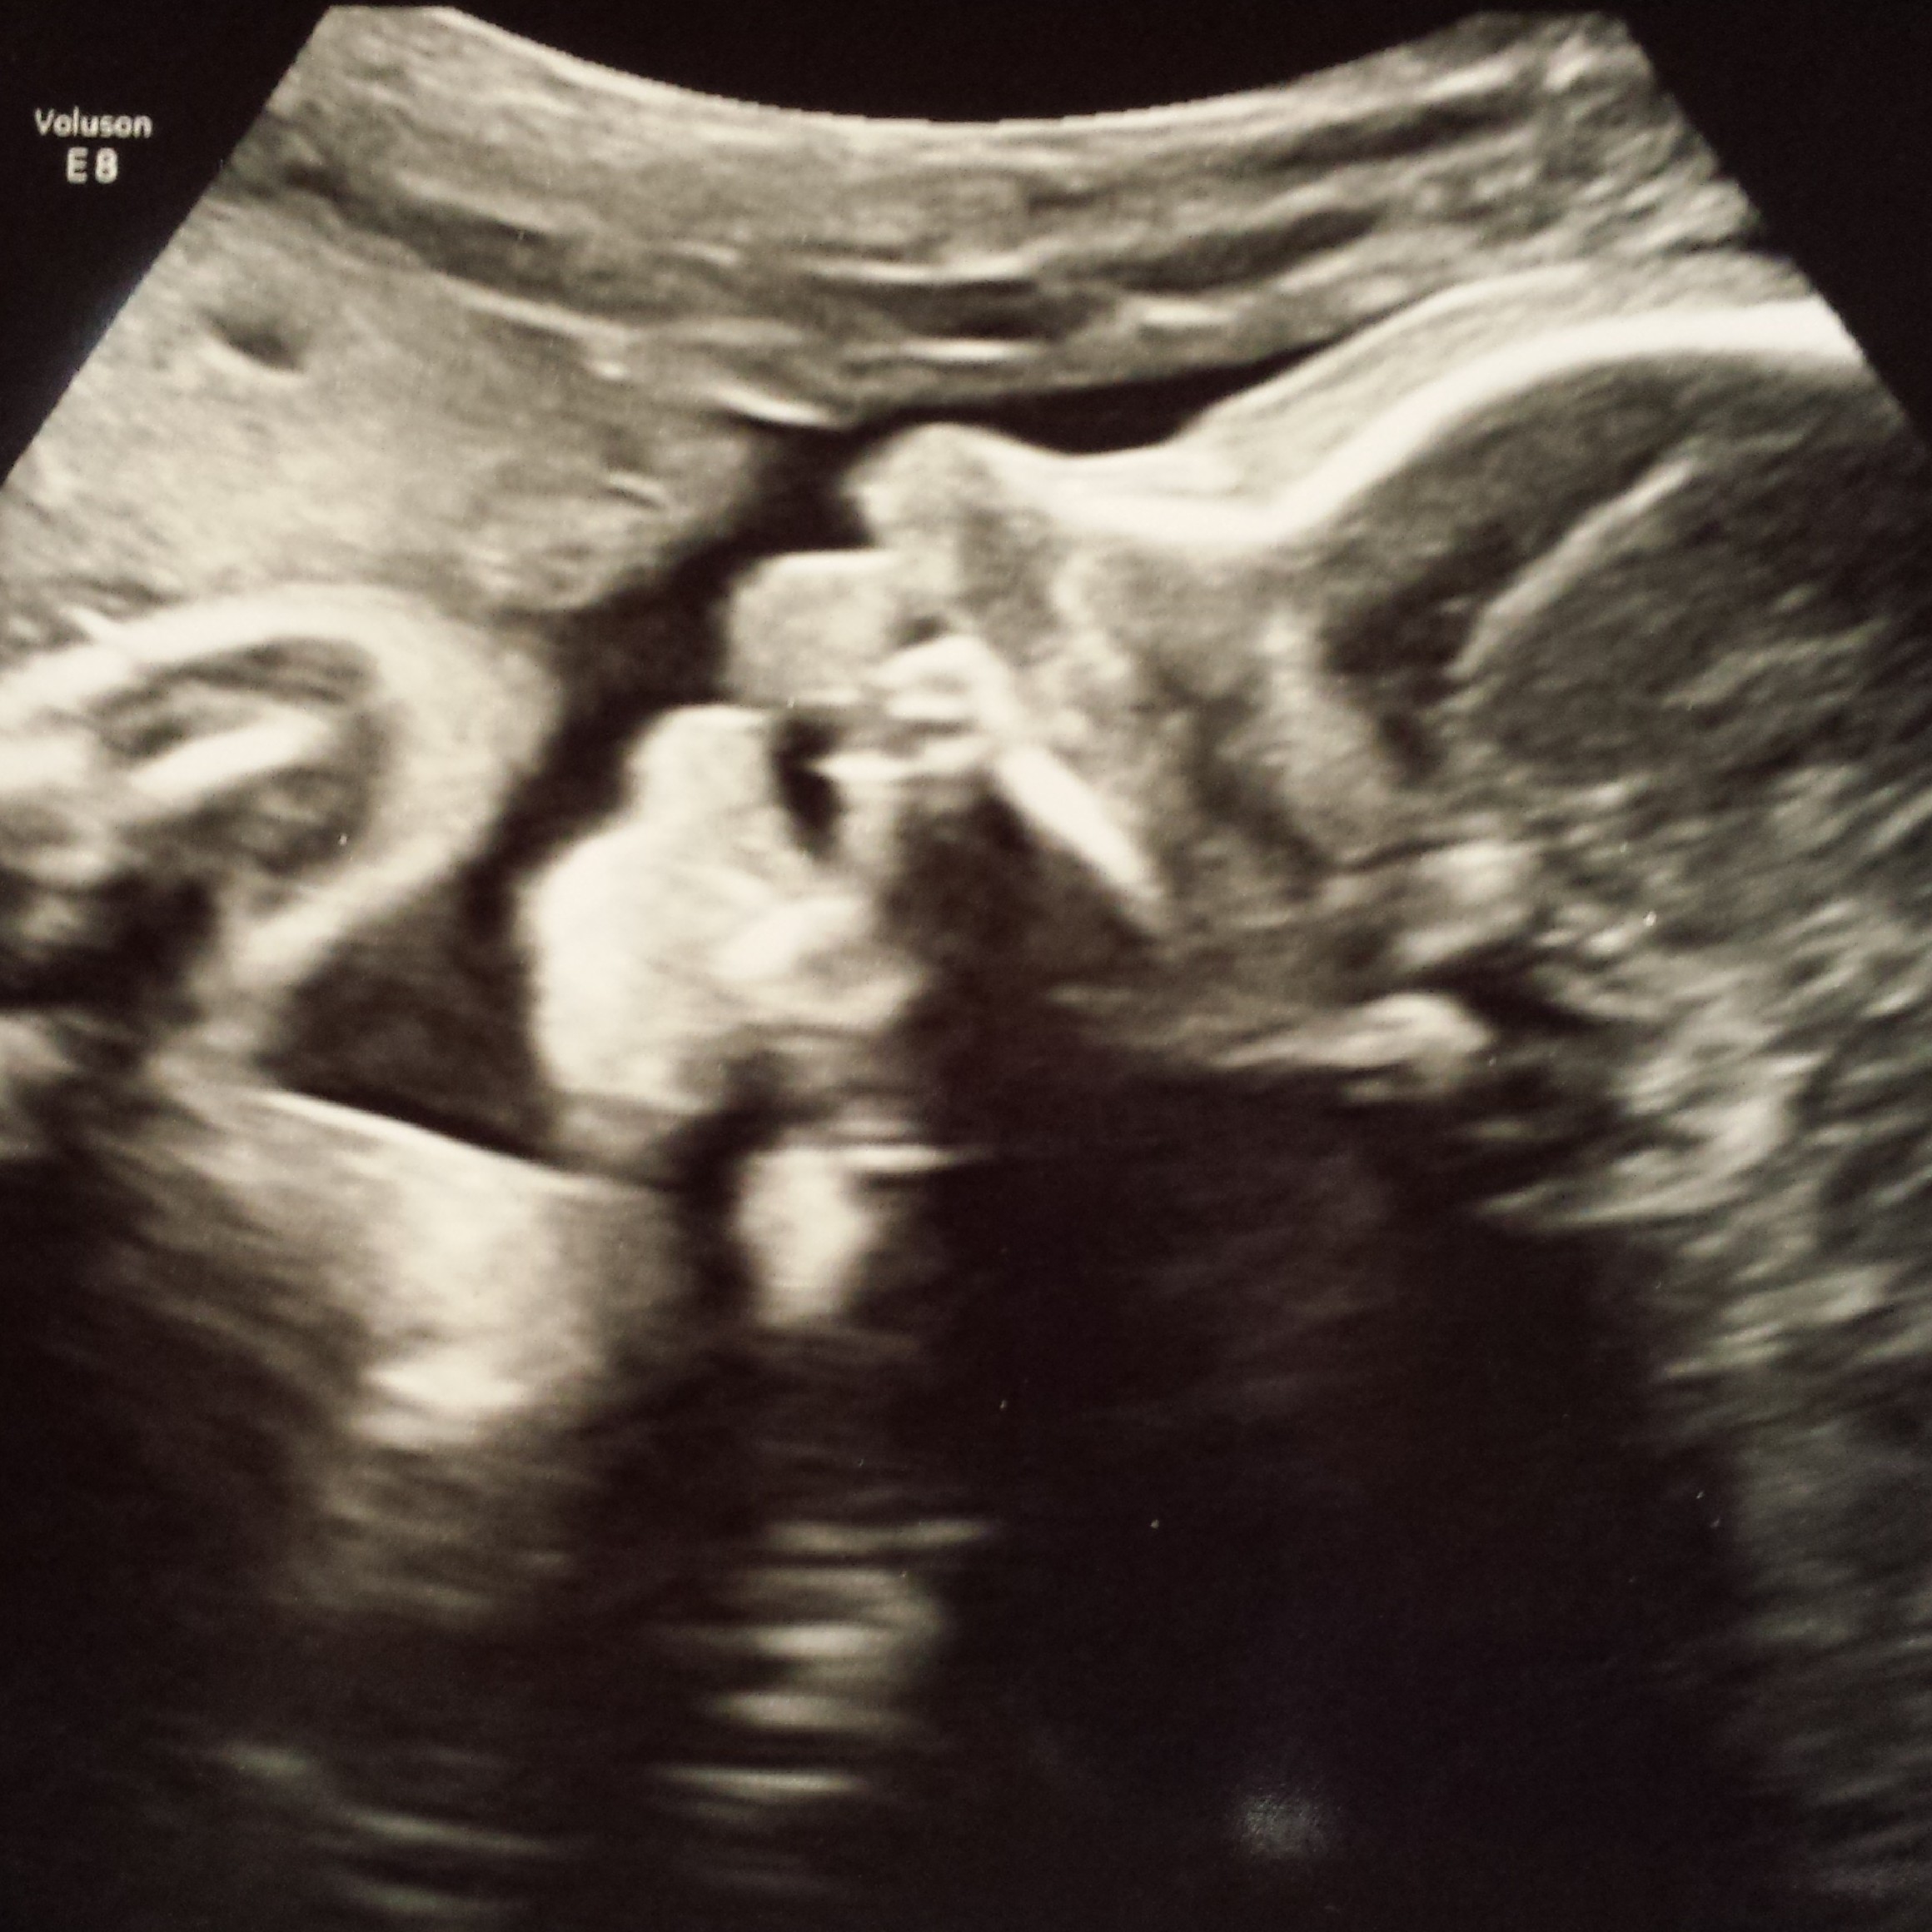

So H and I met with the new doctor today and everything seems to be going well so far. We spent about an hour with ultrasound. We loved seeing him again! He is still measuring right on track which they are happy with since GD usually causes bigger babies. They said he is around 3lb 3oz. And he was doing his practice breathing already which they seemed impressed with. I guess they don't usually start that for a few more weeks.

And here are new pics! He had his hands and arms up in his face the whole time. He did not want to move them at all!